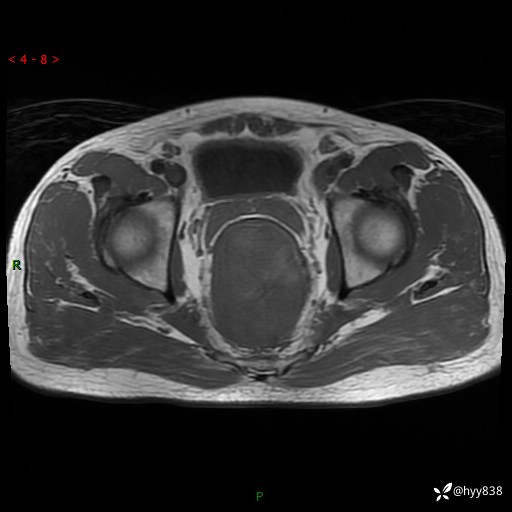

盆腔MRI平扫